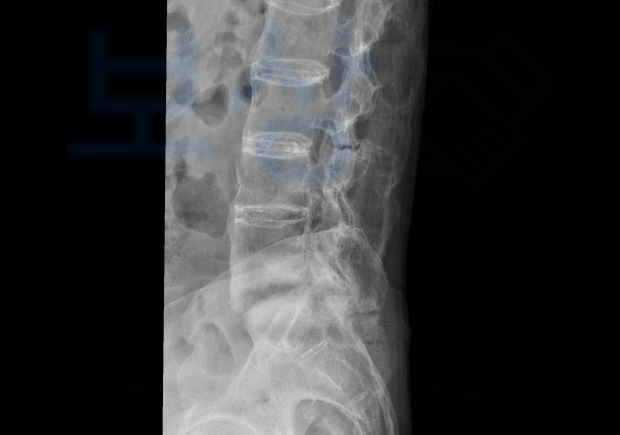

이@@님은 정상차로로 주행하시 던 중 뒤에서 가해 차량이 쿵.. 후미 충돌 사고를 당하셨습니다. 이 사고로 이@@님은 병원에 내원하여 정밀 검사를 받아보시니

제4번, 5번 요추체

압박 골절 진단을 받으셨습니다. 당시 골절의 정도가 심하지 않아 보존적 치료를 시행하게 되었습니다. 먼저 제일 많이 문의주시는 교통사고 합의금은 상담하다보면 안타까운 것이